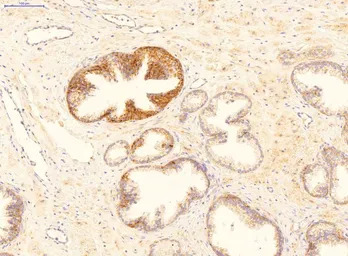

IHC-P analysis of human prostate cancer tissue using GTX46244 GADD45B antibody at 2μg/ml. Leica Bond antigen retrieval solution 1 (citrate buffer, pH 6.0) for 20 min at 99oC.